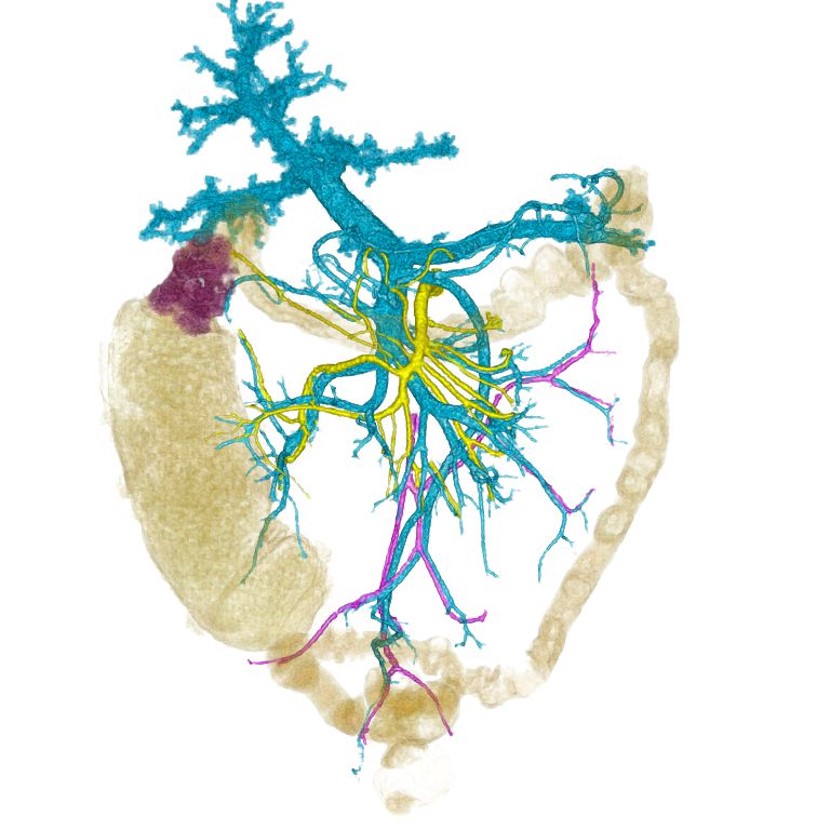

症例5)単純撮影でTEDLが役に立った症例

~造影剤禁忌症例~

肝細胞癌だが造影剤が使えないためplain CTで術前のvolumetryを依頼されました。

残肝容積だけでなく門脈、肝静脈も出来るだけ抽出してほしいとのことで、血管抽出の際にはWWを狭めて作業する必要あるため肝実質と脈管とのコントラストを少しでも上昇させることを目的にTEDLを使用しました。クリニカルIDは最も肝実質のCT値が上昇するdelayedを使用しています。本来TEDLは、単純画像のコントラストを上げる目的で設計はされていませんが、このケースでは改善が見られました。

胆管はMRCP画像とfusionしています。後区域枝が左胆管に合流する解剖変異があり、門脈右枝と胆管との位置関係を術前に把握できました。

「plain CTでもここまで血管や胆管との位置関係を出してもらえると外科医としては助かる」と評価された症例です。

Fig9. 単純撮影でも、TEDLで脈管系が十分に描出できている